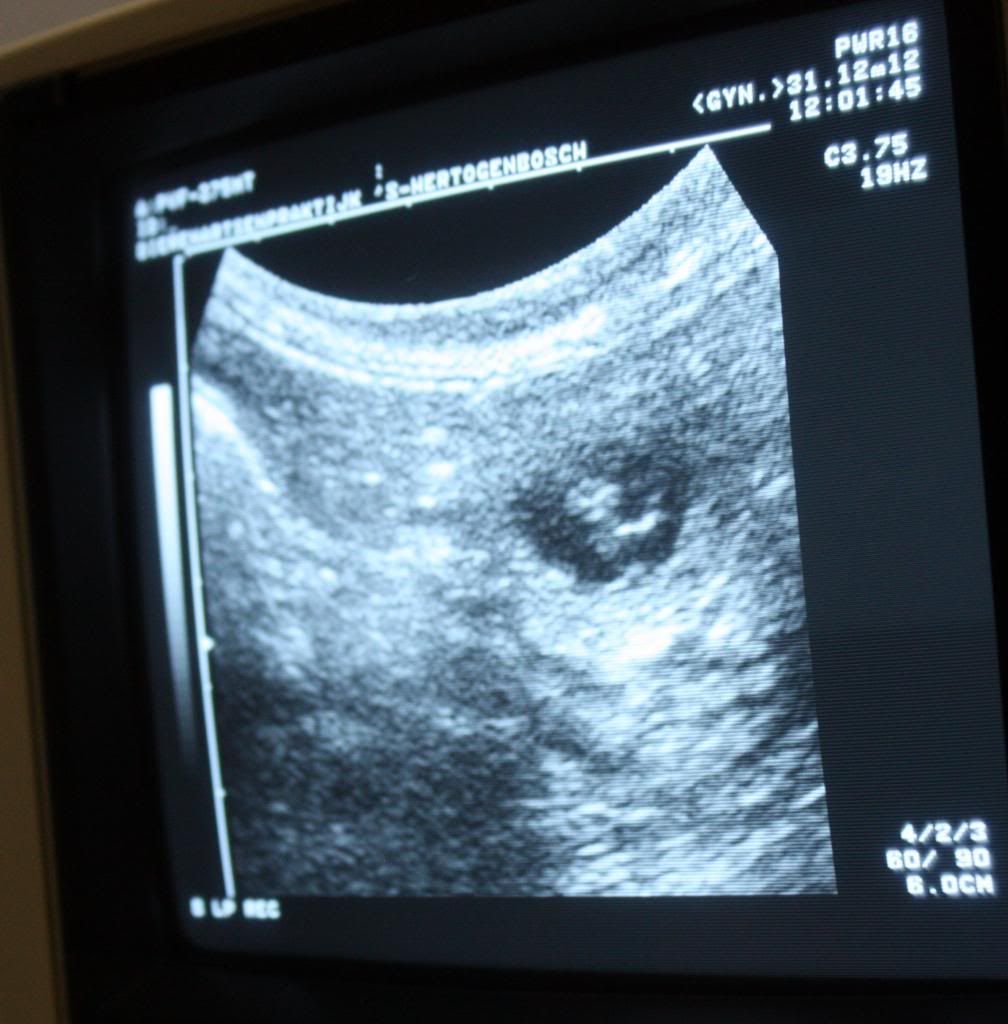

Maandag op de valreep van 2012 gaan we een echo maken.